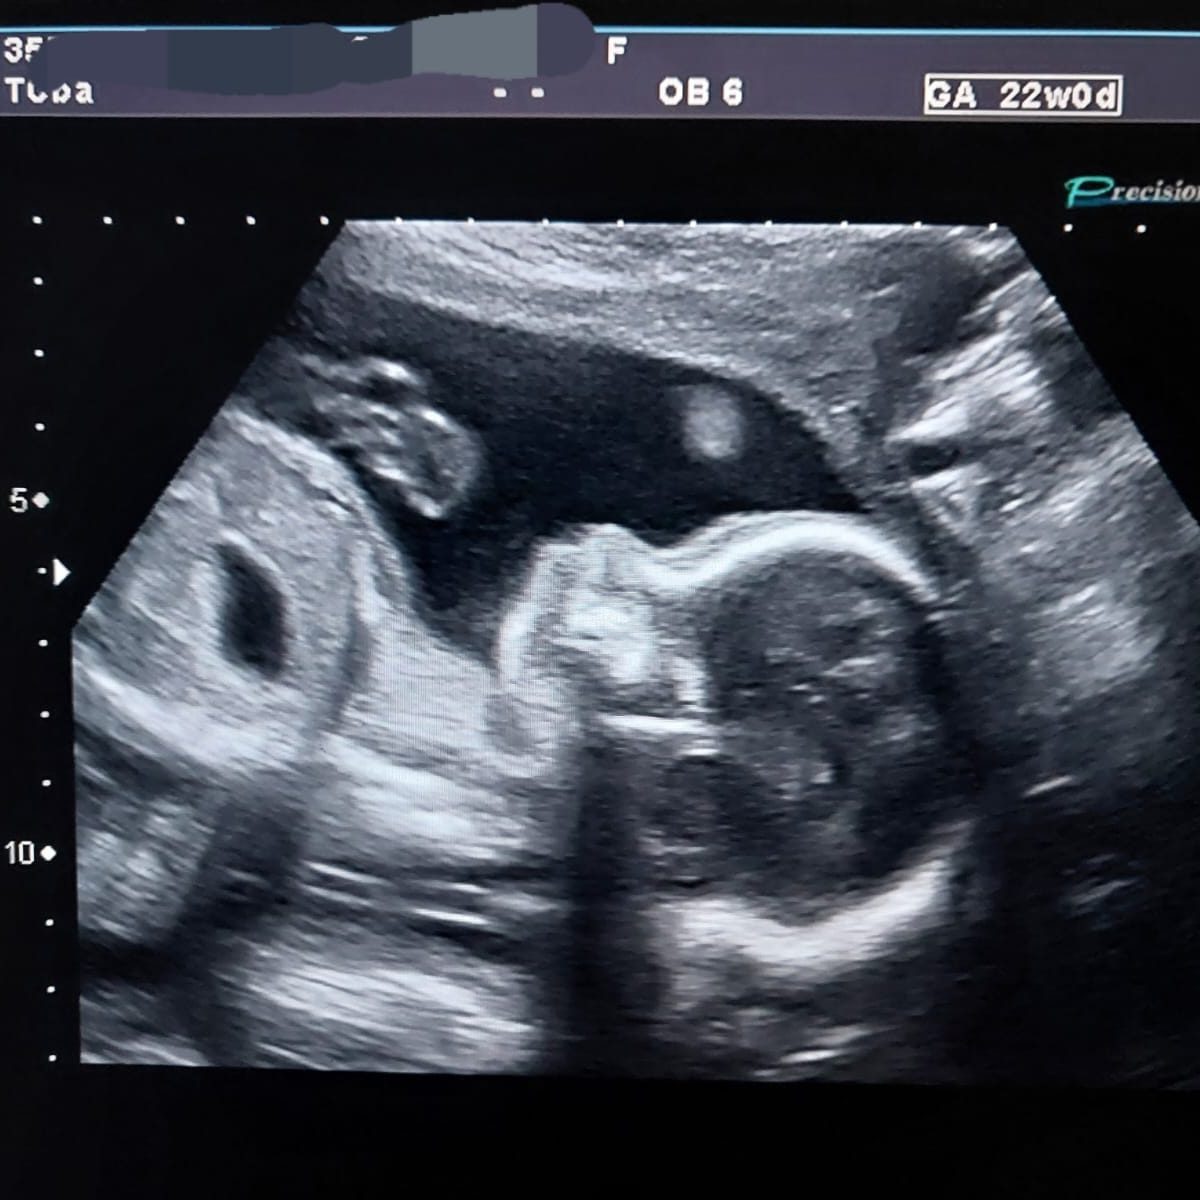

Mi oferta incluye atención integral durante el embarazo, realizando control prenatal de bajo riesgo, ayuda con las molestias en el embarazo, consejería general en alimentación, salud sexual y reproductiva, suelo pélvico, cursos de preparación al parto con y sin pareja, como también de recuperación posparto. Adicionalmente, ofrezco K-Taping.